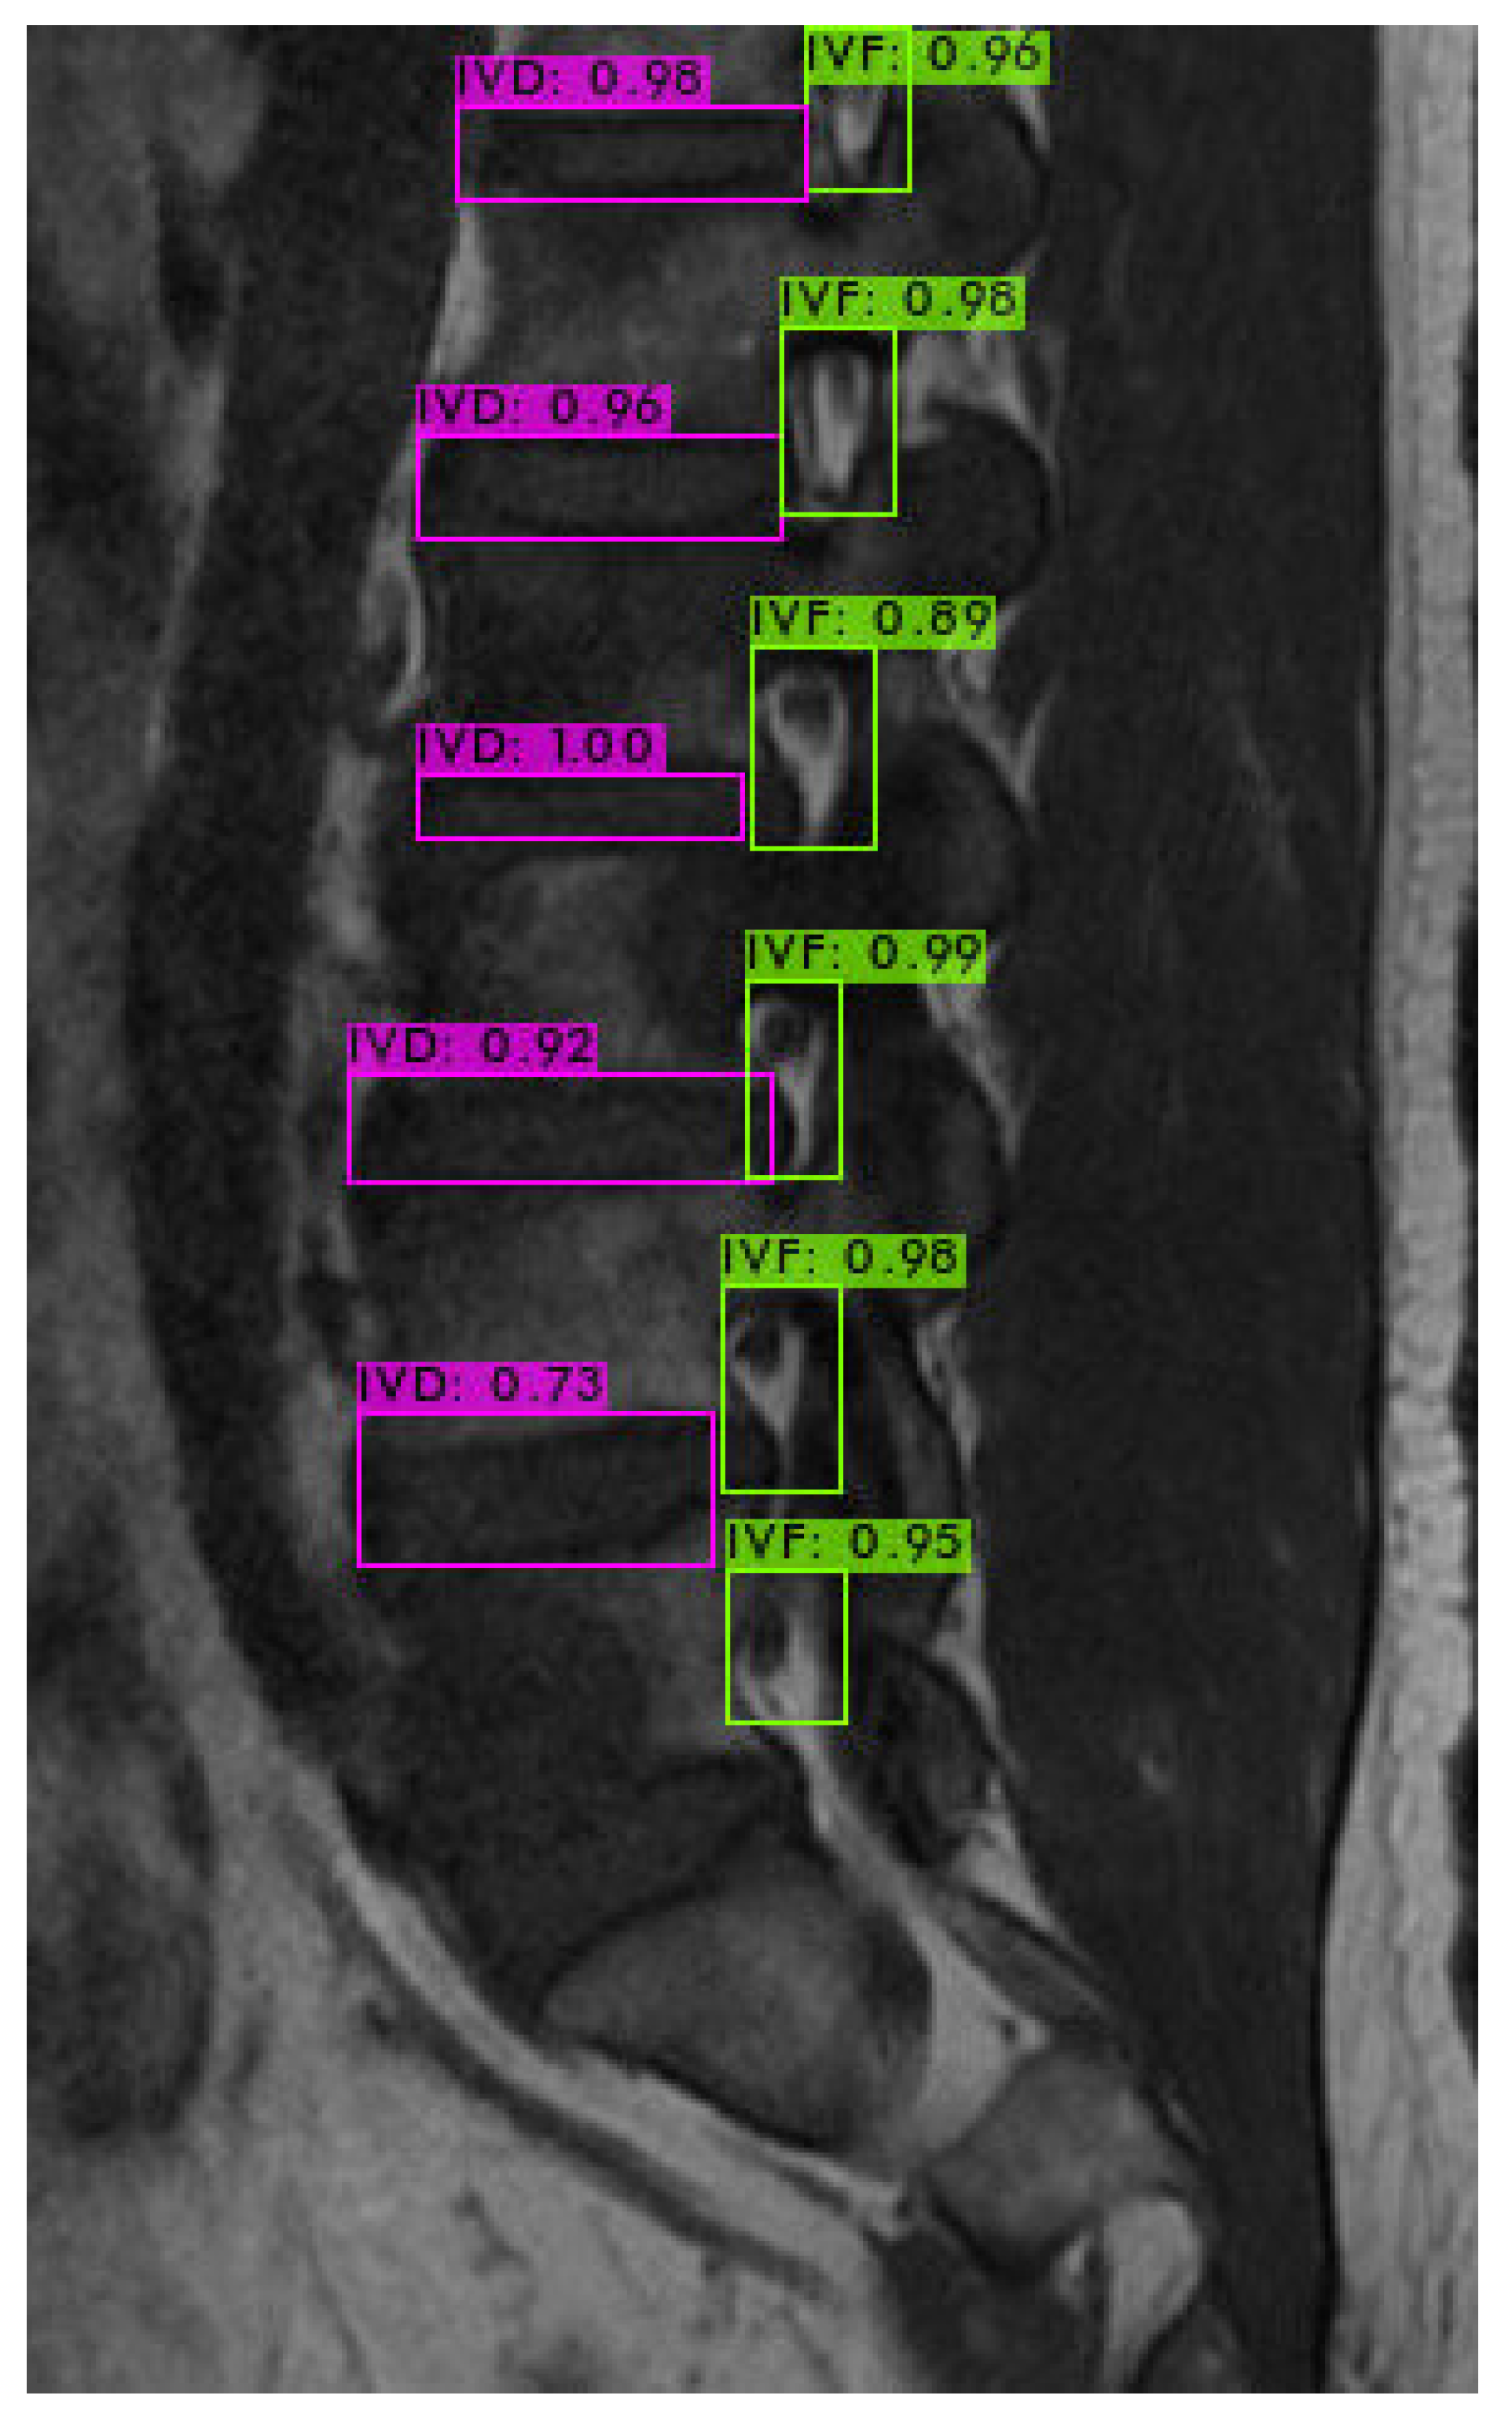

4.3. Intervertebral Foramen Identification